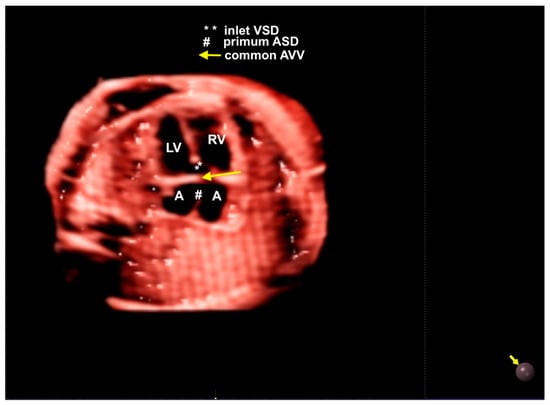

8. Atrioventricular Septal Defect

An atrioventricular septal defect (AVSD) is a CHD that results from the failure of the atrioventricular septum to develop, which can lead to abnormalities of the atrioventricular valves, an ostium primum atrial septal defect (ASD), and an inlet ventricular septal defect (VSD). The complete form of an AVSD is characterized by a common atrioventricular valve, a ostium primum-type ASD, and a large inlet ventricular septal defect (VSD). In other forms of AVSDs, the right and left atrioventricular valves are present with a small VSD or intact interventricular septum. The complete form of an AVSD is strongly associated with syndromes such as trisomy 21. Unbalanced complete AVSD (=marked discrepancy between right and left ventricle) is typically associated with heterotaxy syndromes such as left isomerism. The complete form of an AVSD, can be identified on the 4C view of the fetal heart with color Doppler by an “H-shaped” sign due to the absence of the atrioventricular septum. An AVSD may be associated with other cardiac defects such as tetralogy of Fallot, double outlet right ventricle, and anomalies with outflow tract obstruction. Advanced technologies can provide high-quality images to facilitate early detection during the first trimester cardiac screening in cases with increased nuchal translucency and in complex cases, such as it is when associated with other cardiac anomalies (Figure 16 and Figure 17) [2,3,6,48].

Figure 17.

Realistic Vue with Natural Vue and Transparency mode in a case of complete atrioventricular septal defect. Note the high quality of the image. Virtual light source position; 10 o’clock. LV: left ventricle; LA: left atrium; LV: left heart; RV: right ventricle; VSD: ventricular septal defect; ASD: atrial septal defect; AVV: atrioventricular valve.